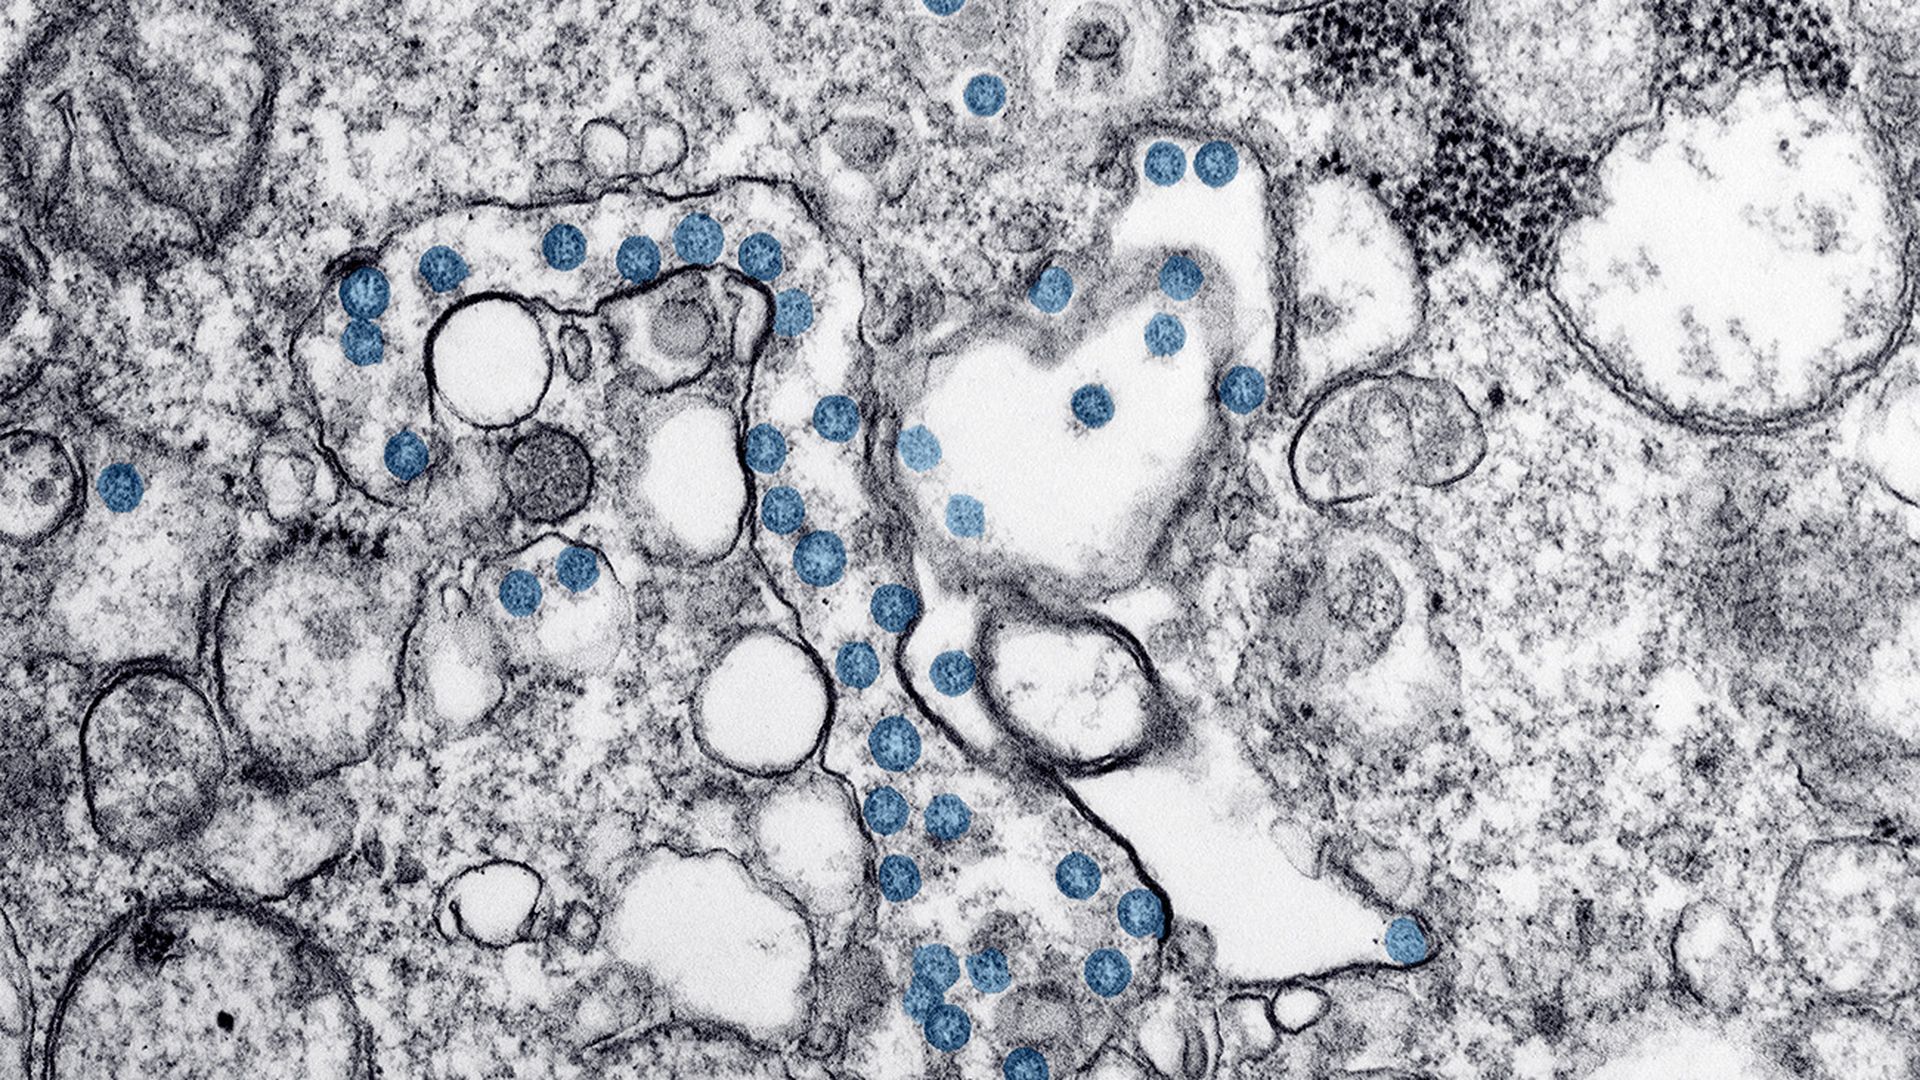

COVID-19-image-cdc coronavirus